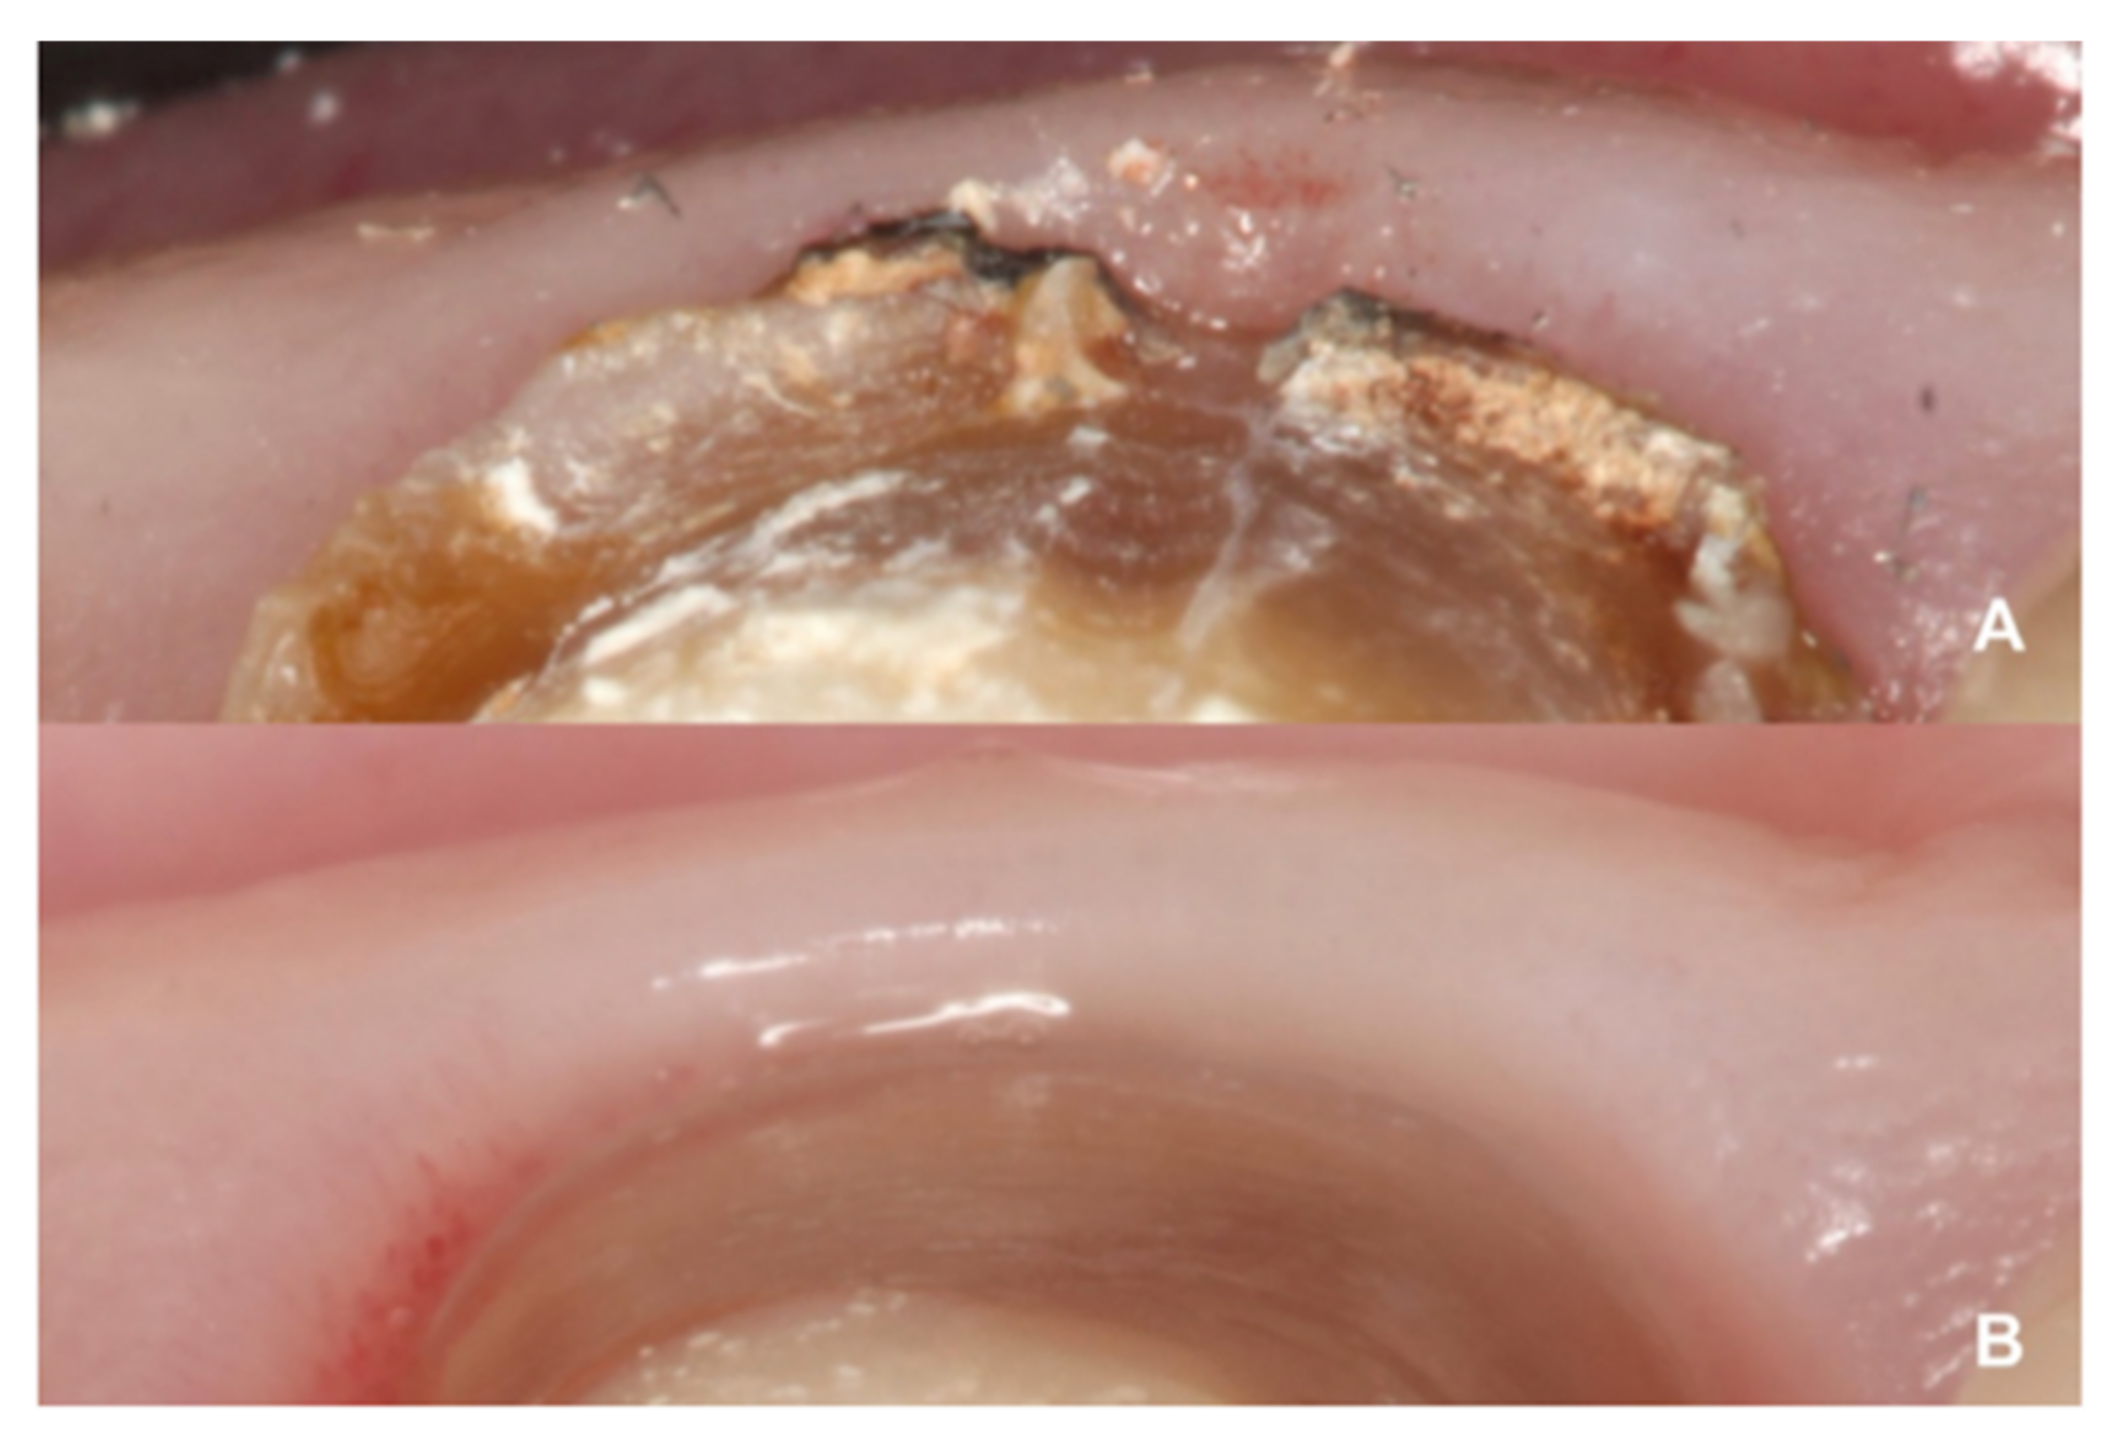

- Treatment with a fixed prosthesis using the BOPT technique has a positive impact on patient satisfaction, especially in cases concerning the re-treatment of old fixed prostheses. This fact is due to the esthetic improvement not only of the restoration but also of the surrounding tissues, as it improves gingival quality by thickening the tissue, thus preventing gingival recession.

- Agustín-Panadero, R.; Solá-Ruíz, M.F. Vertical preparation for fixed prosthesis rehabilitation in the anterior sector. J. Prosthet. Dent. 2015, 114, 474–478. [Google Scholar] [CrossRef] [PubMed]